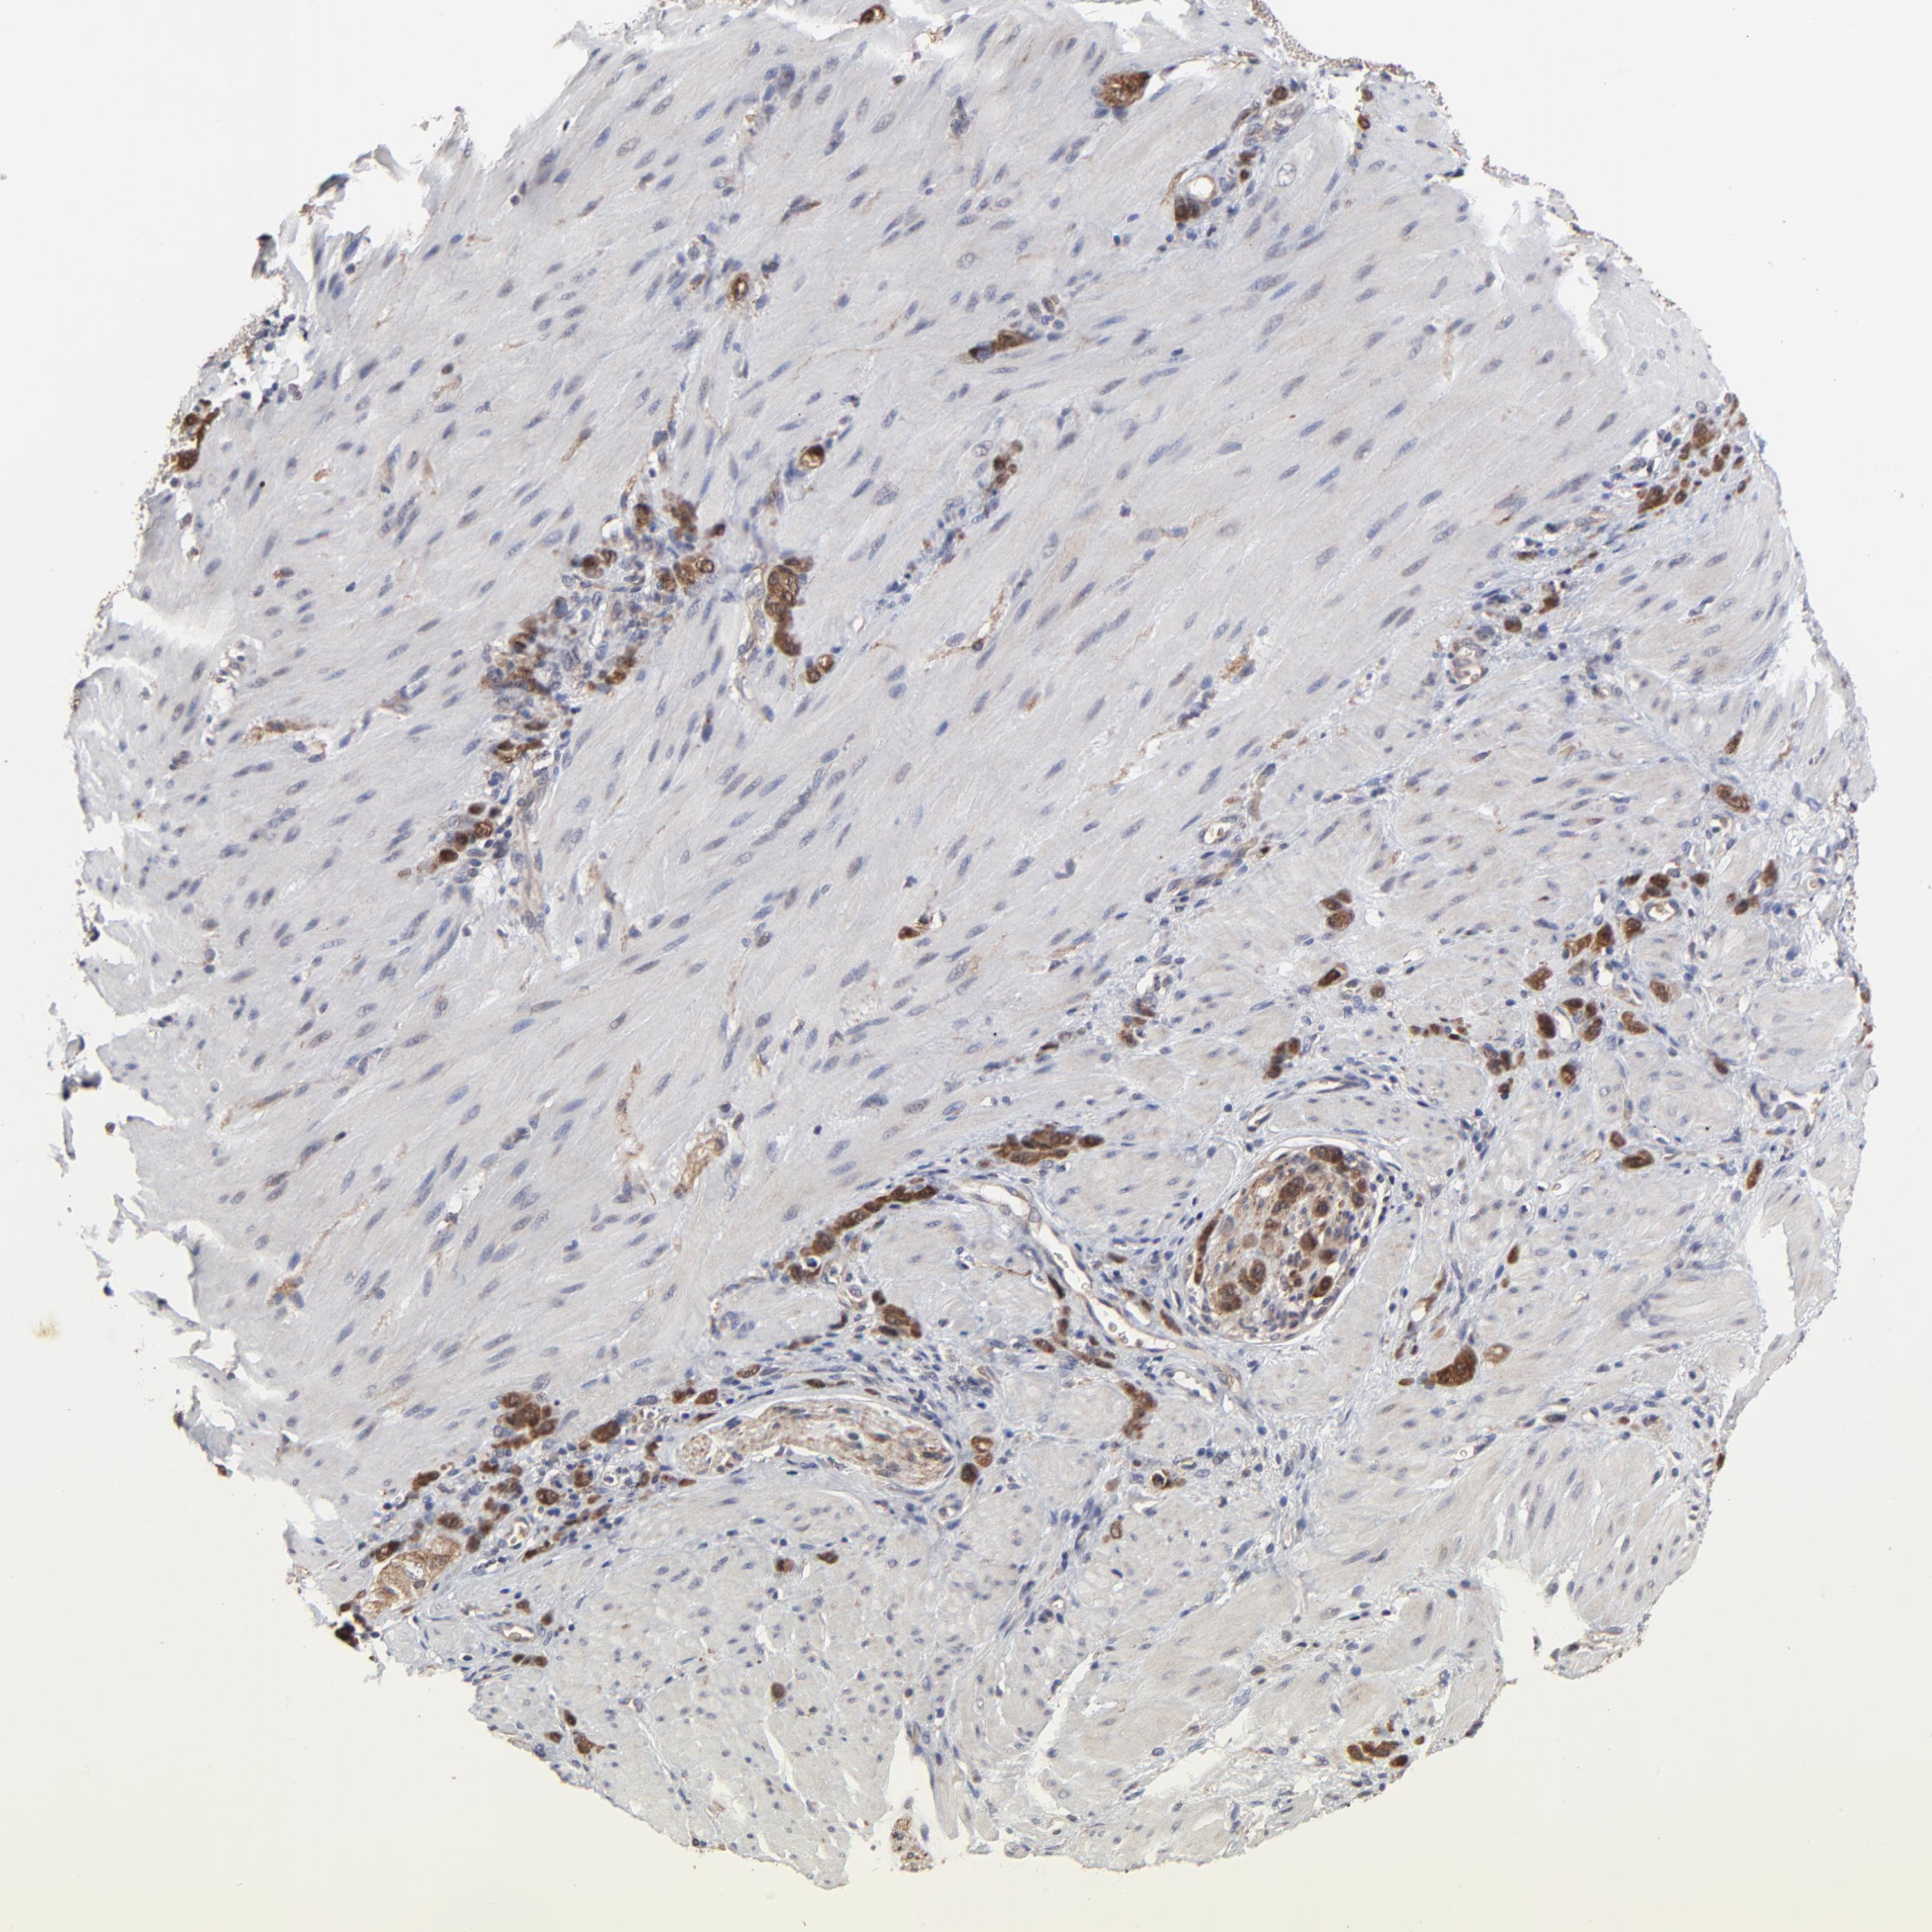

STOMACH CANCER - Protein expressioni

A mouse-over function shows sample information and annotation data. Click on an image to view it in a full screen mode. Samples can be filtered based on level of antibody staining by selecting one or several of the following categories: high, medium, low and not detected. The assay and annotation is described here.

Note that samples used for immunohistochemistry by the Human Protein Atlas do not correspond to samples in the TCGA dataset.

Antibody stainingi

Antibody staining in the annotated cell types in the current human tissue is reported as not detected, low, medium, or high, based on conventional immunohistochemistry profiling in selected tissues. This score is based on the combination of the staining intensity and fraction of stained cells.

Each image is clickable and will lead to virtual microscopy that enables deeper exploration of all samples and also displays staining intensity scores, fraction scores and subcellular localization as well as patient and tissue information for each sample.

Antibody HPA002861

Staining

High

Medium

Low

Not detected

Intensity

Strong

Moderate

Weak

Negative

Quantity

>75%

75%-25%

<25%

None

Location

Nuclear

Cytoplasmic/membranous

Cytoplasmic/membranous,nuclear

Adenocarcinoma, NOS

Adenocarcinoma, High grade